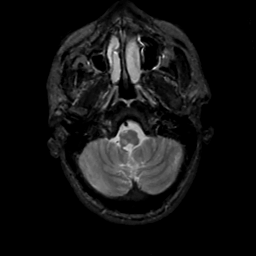

MR Study #12, May 12, 1991 -- Slice #7